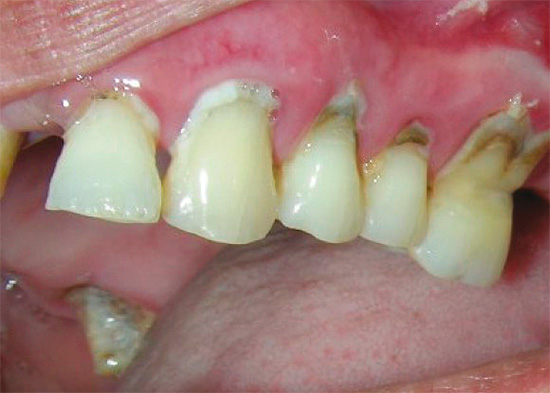

É importante distinguir entre um defeito em forma de cunha e cárie cervical: eles diferem em que o primeiro está na forma de uma cunha ou em forma de V. Com um defeito em forma de cunha, as paredes da cavidade são densas, lisas e brilhantes, o que não se pode dizer sobre a destruição cariosa do dente na região cervical.

Apesar de a localização dessas doenças ser a mesma, a aparência da cavidade sempre informa ao médico o diagnóstico correto. Além disso, as formas iniciais de cárie e um defeito em forma de cunha podem ser reconhecidas quando manchadas com indicadores especiais de cárie.

Na foto, você pode comparar o defeito em forma de cunha e a cárie cervical: